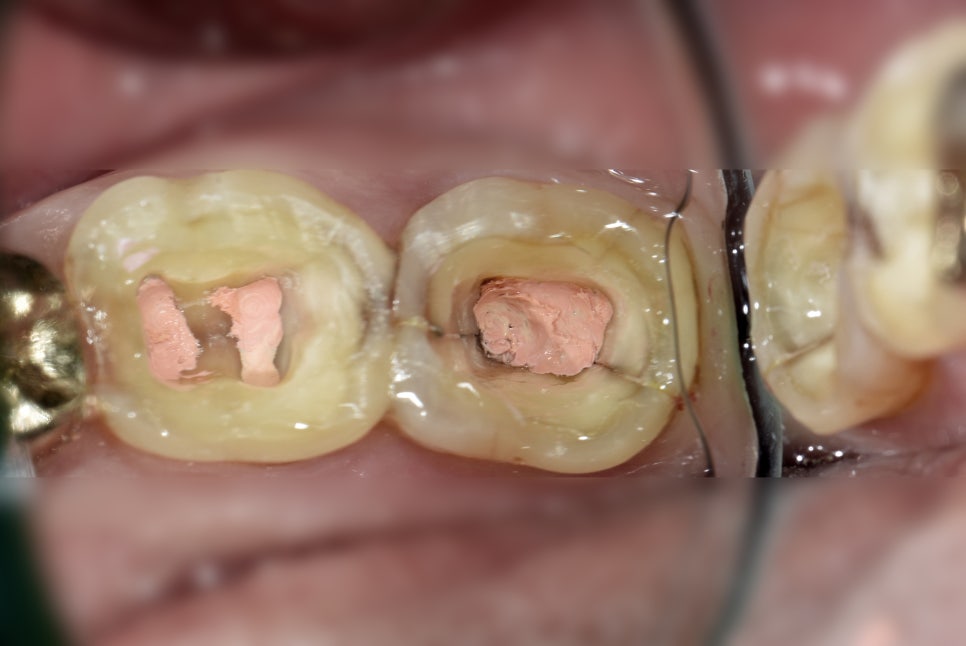

금요일 오늘의 케이스는, 코어+프렙 하는 날인데 그동안 아프셨다고.. 그래서 일단 여러가지 설명 드리고 캐비톤 열어서 확인해봤는데 저런 상태였다. 원래 엔도 시작할 때 AO하면서 크랙 찍어놓은 사진과 비교하면 틈이 확실히 더 벌어졌다. 변색도 심해졌다. 상부엔 캐비톤이 끼어있을 정도였다. 사진 확대하면 crack line 깊은 부위(root portion)에도 턱이 진 게 보일 정도다. 이거는 cracked tooth가 아니고 split tooth다.. 그래도 당장 발치하지는 않았고 환자분께서 받아들일 시간(?)을 주기 위해서 코어 접착해드리고 다음 번 내원에 증상 남아 있으시면 발치해야한다고 조심스럽게 사진 보여드리면서 자세히 설명드렸다.

엔도 시작할 때 와동 내에서까지 관찰되는 crack은 항상 DSLR사진 찍어 1일차(AO+pulpotomy) 마친 후에 의자 세워드리고 따로 예후 불량을 설명드리지만, 이렇게 마무리하고 발치 설명드리는 건 참 어려운 일인 것 같다.